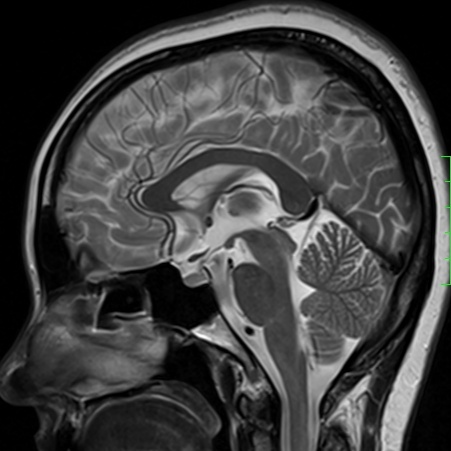

磁共振——锁定“水”的科技

磁共振(MRI)与普通X线、CT不同,不依赖于X线成像,而是氢原子核,也可以理解为水。以前称为核磁共振,是因为MRI的原理是用较大的磁场,使人体内原本随意排列的氢原子核磁场的磁力线方向统一,再突然把磁场的作用去掉,监测其中信号的变化。MRI成像依靠不同组织含氢核数目不同,或者可以近似理解为不同组织含水量不同,形成图像差异,来区别组织。所以MRI对中枢神经系统和软组织有着良好的分辨能力,适用于软组织、神经系统疾病、内脏器官,并且多序列及多参数成像、功能成像。不过,MRI检查时间较长,价格较贵,预约时间较长。

磁共振平扫图像